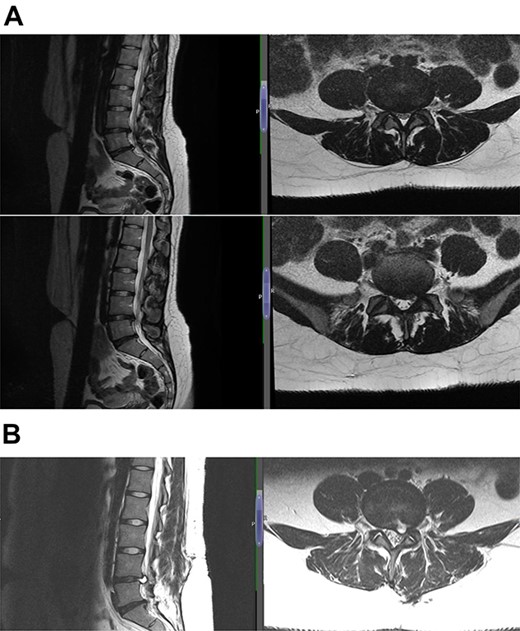

The diagnosis was reached keeping in mind the radiological and contrast scan was taken in follow-up period (Figs 1, 2a, b,3a, b and4a, b). On MRI, it was noted that the cyst was well-defined, smooth regular margins with T1 hypointense and T2 hyperintense and an evident communicating stalk with the disc while in post-gadolinium scan showed cyst wall enhancement. As discography is no longer required for reaching a diagnosis, it was not done in any of the patients.

(A) Case 4—an initial MRI showing multilevel degenerative disc disease and a cyst at the lumbar L5/S1 which is causing impingement on the left S1 nerve root, and (B) case 4—comparison was made with the previous MRI; post-contrast scan shows that the L5-S1 left-sided cystic features have nearly diminished; no neoplastic lesion is detectable.